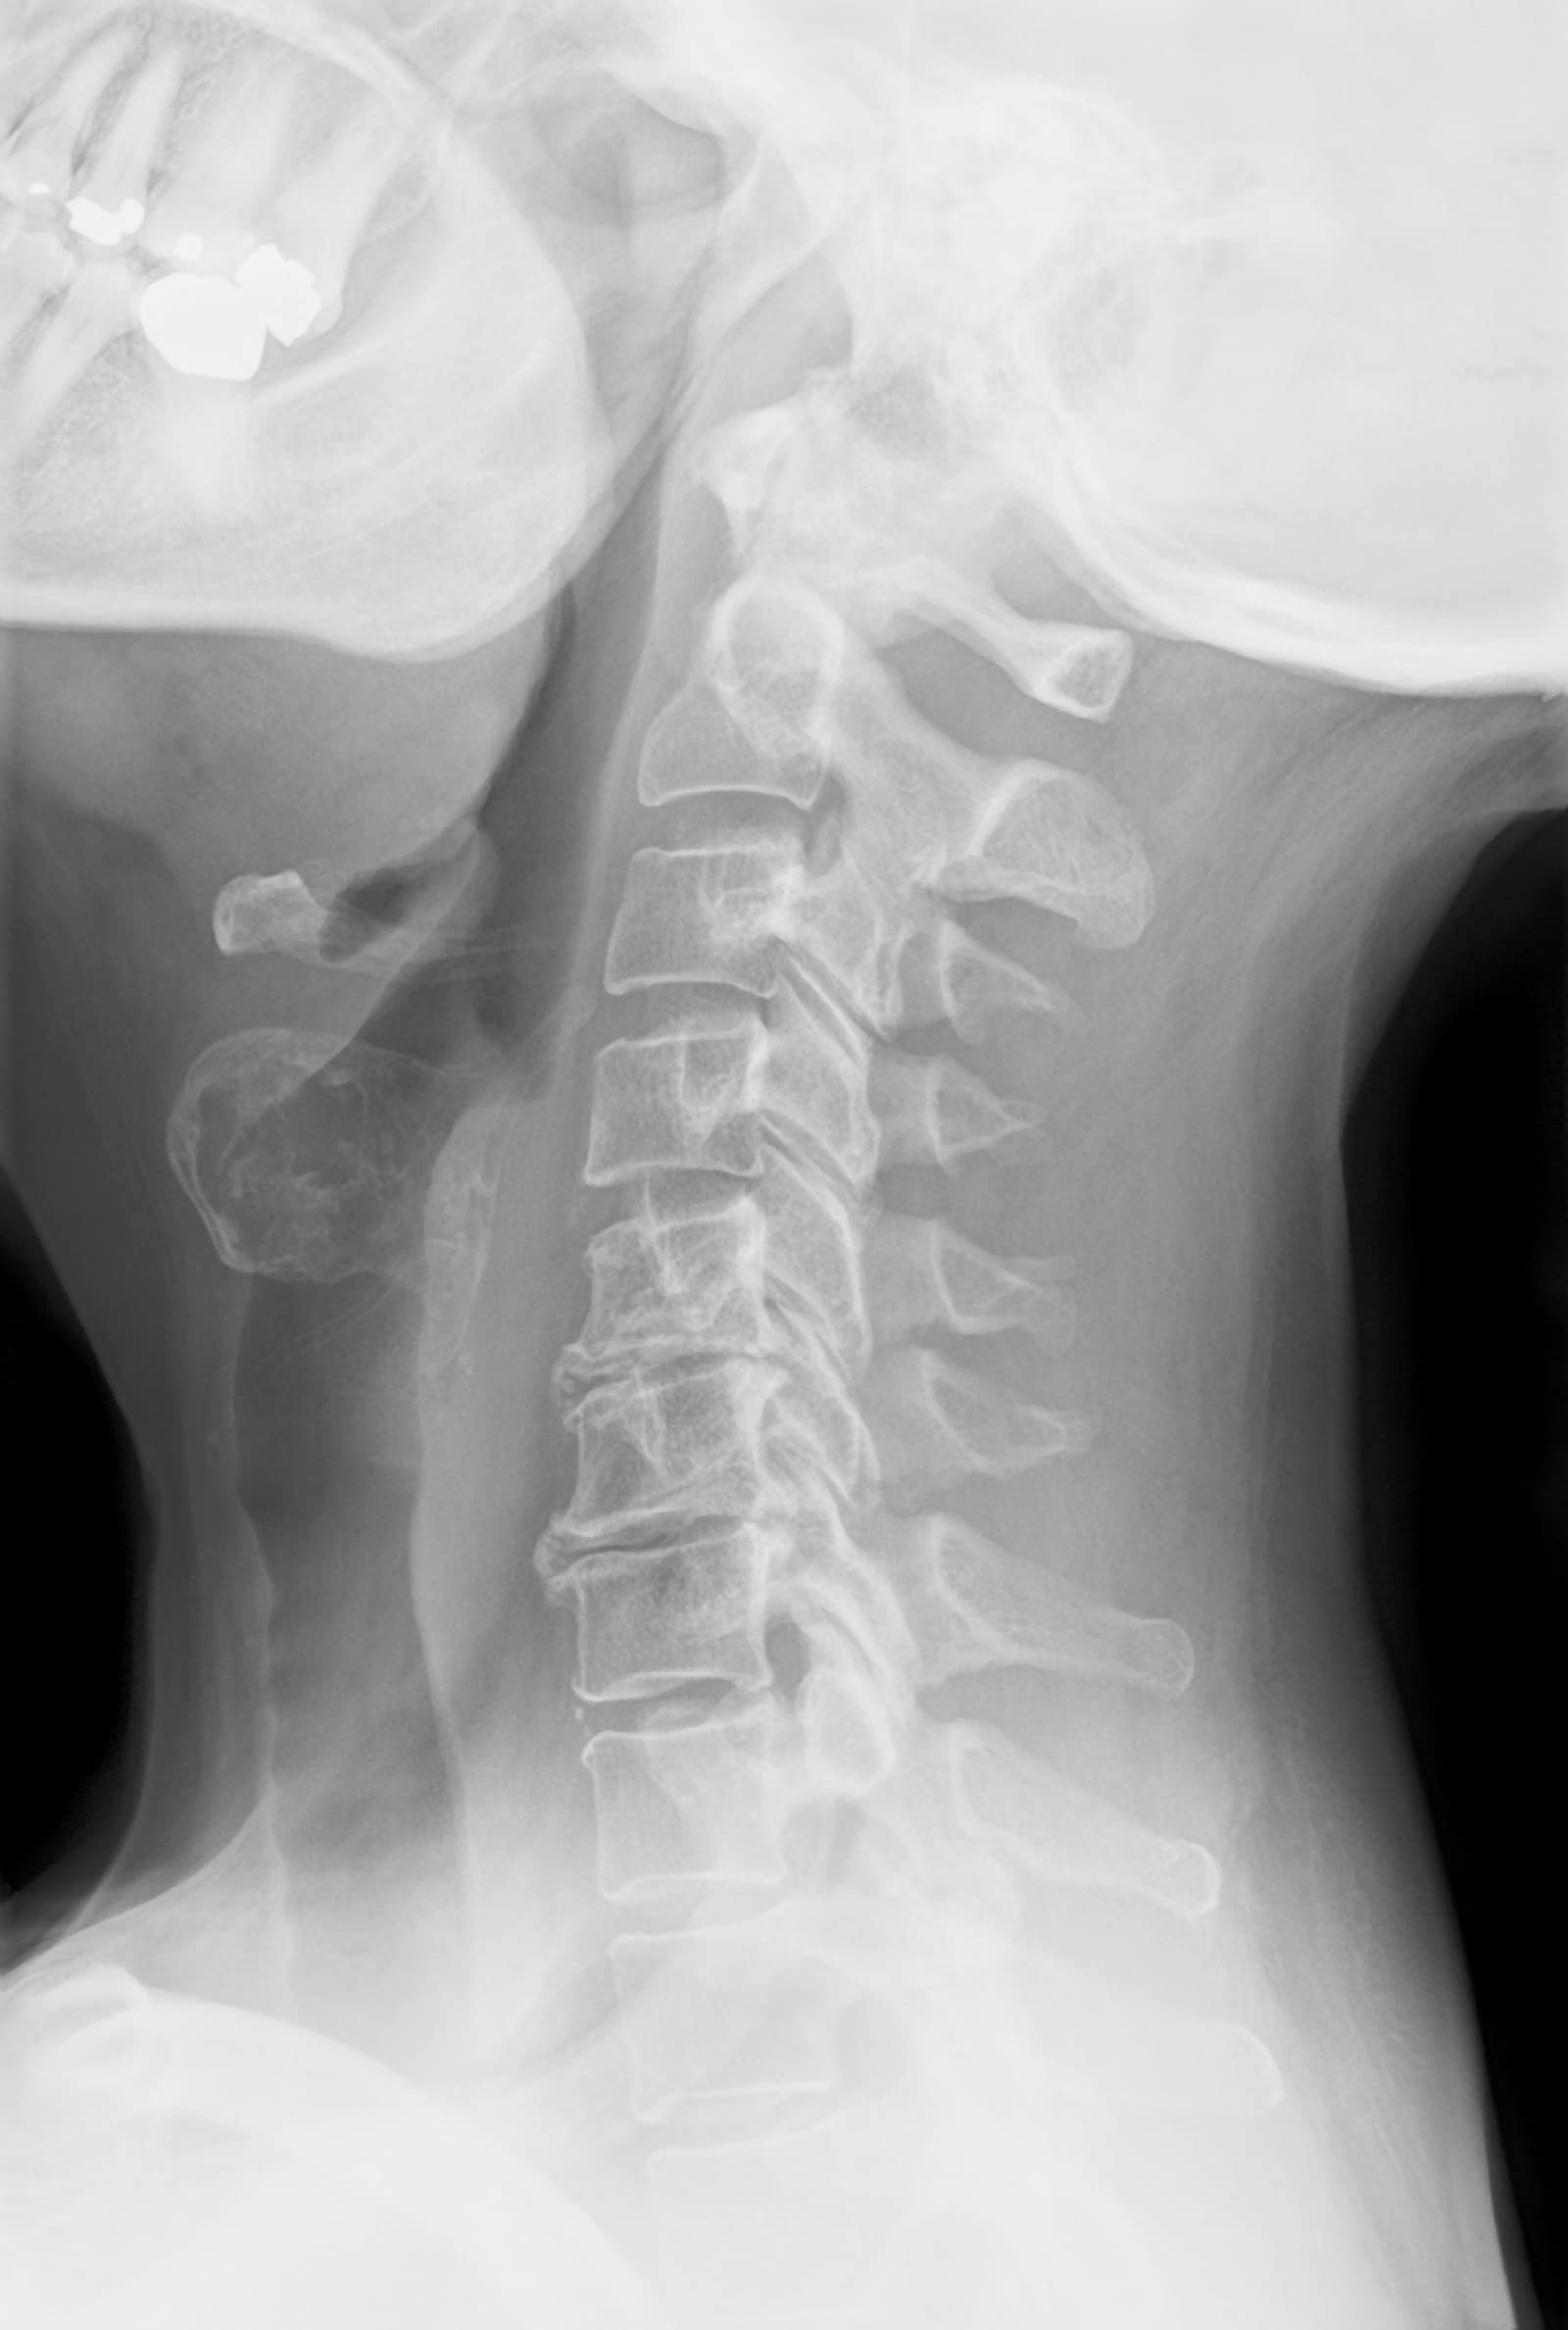

| Prue’s X-ray |

Normal X-ray |